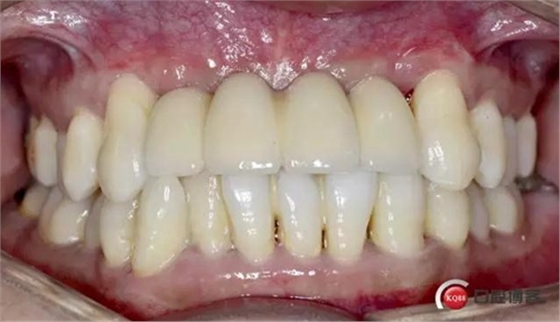

戴牙完成

個(gè)人心得:

前牙區(qū)牙周病骨缺失嚴(yán)重,擔(dān)心成骨效果欠佳先行GBR沒(méi)有同期植入

充分骨整合時(shí)間,植入風(fēng)險(xiǎn)降低且效果穩(wěn)定。

需要患者有較高的一從性,定期復(fù)查

種植周期延長(zhǎng)